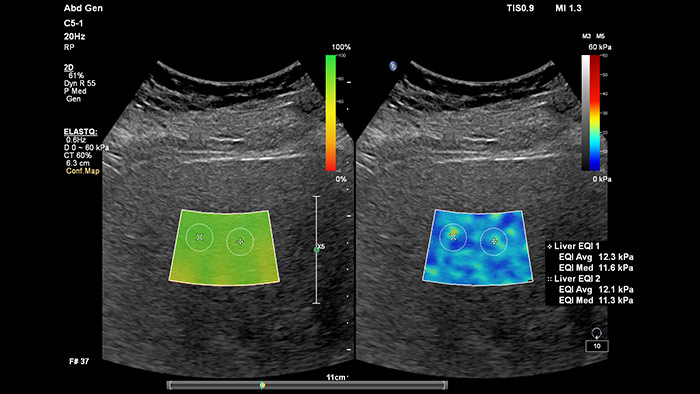

Elastografía por onda transversal de imágenes con ElastQ

La elastografía por ultrasonidos de onda transversal ofrece un método no invasivo, reproducible y fácil de poner en práctica para evaluar la rigidez tisular. Los estudios realizados apuntan a que, en lugar de un costoso y doloroso procedimiento de biopsia, una sencilla exploración por ultrasonidos con elastografía de onda transversal podría convertirse en el procedimiento habitual para evaluar el estado de las enfermedades hepáticas. La elastografía por onda transversal de alto rendimiento de las imágenes con ElastQ incluye la evaluación cuantitativa de la rigidez tisular, codificada con colores, en extensas regiones de interés (ROI) en tiempo real. Las imágenes con ElastQ también ofrecen la posibilidad de efectuar mediciones retrospectivas en imágenes almacenadas; además, una exclusiva pantalla con un mapa de confianza emplea el análisis inteligente para ofrecer la garantía adicional de que las mediciones del usuario se han obtenido en zonas tisulares con una propagación adecuada de ondas transversales.

Evaluación hepática no invasiva simplificada

La medición de la rigidez hepática se obtiene en cuestión de segundos por medio de una sencilla exploración no invasiva.